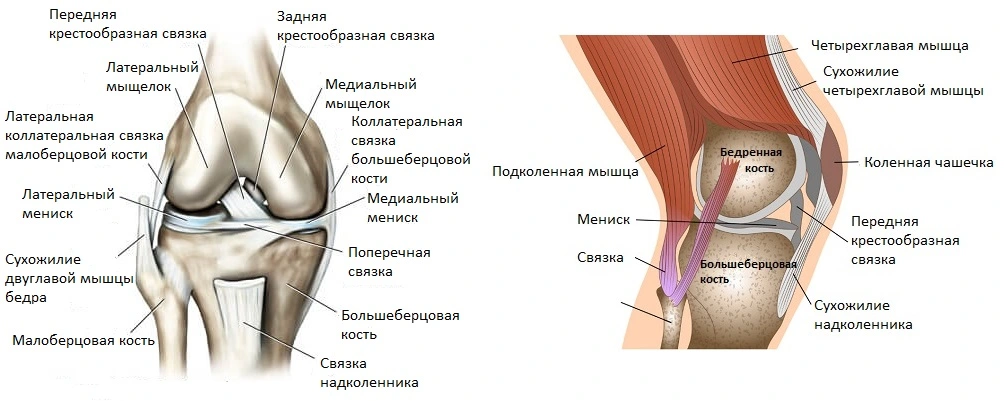

Возможные причины болей в ноге ниже колена и рекомендации